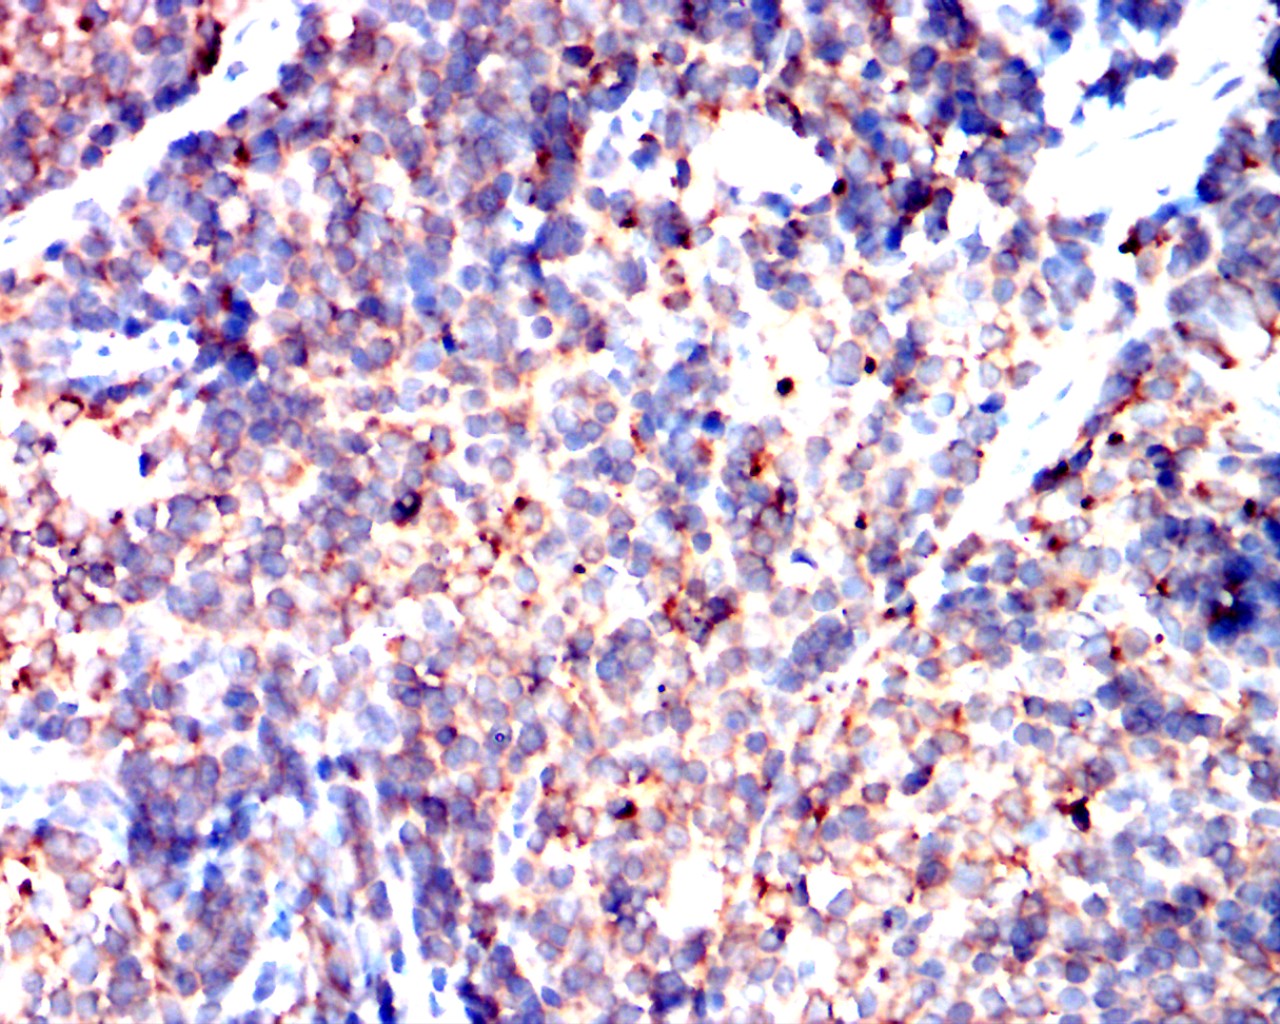

Immunohistochemical analysis of paraffin-embedded human cervical cancer showing cytoplasmic localization using PIK3CA mouse mAb with DAB staining.

Immunohistochemical analysis of paraffin-embedded human colon cancer showing cytoplasmic localization using PIK3CA mouse mAb with DAB staining.

Immunohistochemical analysis of paraffin-embedded mouse spleen showing cytoplasmic localization using PIK3CA mouse mAb with DAB staining.

Immunohistochemical analysis of paraffin-embedded rat spleen showing cytoplasmic localization using PIK3CA mouse mAb with DAB staining.